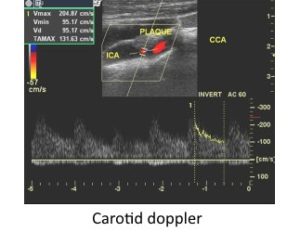

Carotid Color Doppler: Carotid Doppler is specifically meant for assessment of blood vessels that supply the brain. Carotid arteries are the major vessels which carry blood to the brain.

Carotid Color Doppler: Carotid Doppler is specifically meant for assessment of blood vessels that supply the brain. Carotid arteries are the major vessels which carry blood to the brain.